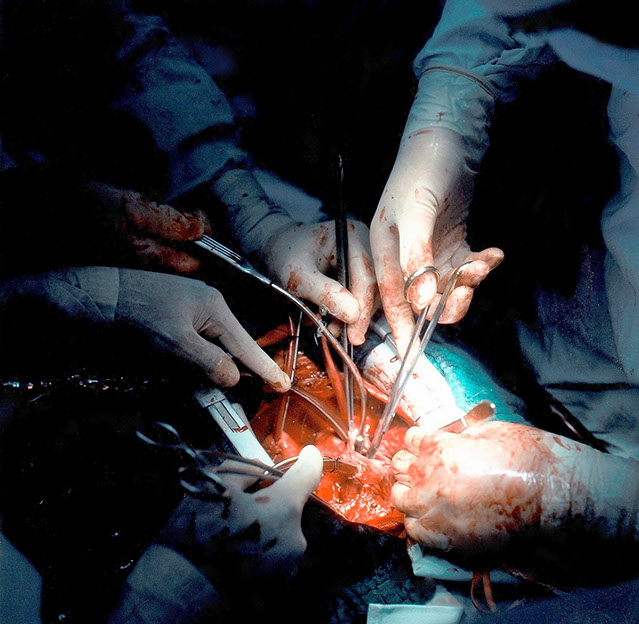

FOTO-DOKUMENTATIONEN